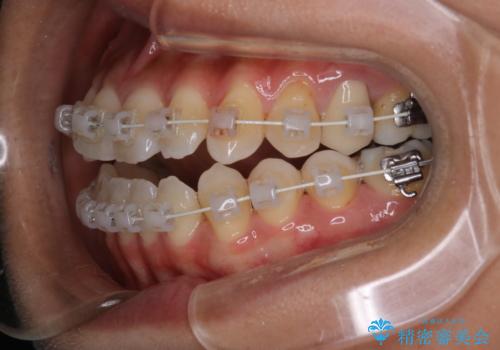

- 開咬を主訴に来院されました。前歯部に開咬、右側大臼歯部にクロスバイトが認められます。ワイヤー矯正の審美装置で治療し、ゴム掛けを行いながら噛み合わせを改善しました。

主訴である開咬と右側大臼歯部クロスバイトを改善でき、しっかりと噛むことができるようになりました。